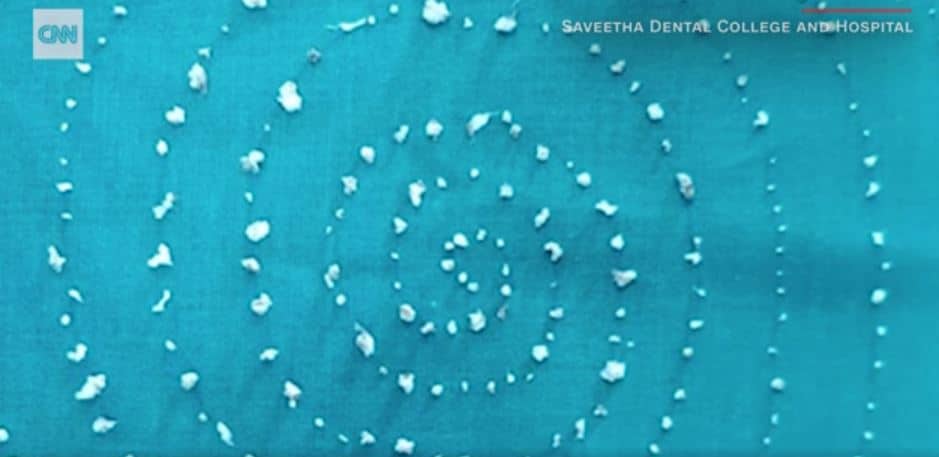

India, etratti 526 denti dalla bocca di un bambino di 7 anni: “Primo caso simile mai riportato al mondo”

Estratti 526 denti dalla bocca di un bambino

526 denti trovati nella bocca di un bambino di 7 anni in India.

Il piccolo si lamentava per il fortissimo dolore alla mascella, e così si è recato al Saveetha Dental College and Hospital di Chennai, nello stato del Tamil Nadu.

I dentisti dell’ospedale hanno estratto oltre 500 denti dalla sua bocca, in un’operazione durata circa 5 ore, durante la quale i medici hanno trovato dei denti “anormali”, diversi dai molari che normalmente crescono nella bocca dei bambini adulti.

“Ogni dente assomigliava a un piccolo dente con una corona e una struttura simile a una radice”, riporta l’emittente televisivo statunitense Cnn.

I medici del Saveetha Dental College and Hospital di Chennai hanno dichiarato che si tratta del primo caso di questo tipo mai documentato al mondo. Le dimensioni dei denti andavano da 0,1 a 15 millimetri.

Stando alla Tac prescritta dai dottori prima dell’intervento, a generare la crescita esponenziale di denti all’interno della bocca del bambino di 7 anni, è stata una specie di sacca: una sorta di tumore che impediva la crescita regolare dei molari del piccolo, al cui interno erano invece racchiusi i 526 denti anormali.

Dr. Prathiba Ramani, a capo del dipartimento in cui è stato operato il bambino nell’ospedale di Chennai, ha fatto sapere che tutto è andato per il meglio e che ora il paziente è in ripresa.

La rara massa all’interno della mascella del piccolo potrebbe aver avuto un’origine genetica, ma i dottori stanno ancora indagando sul caso per saperne di più.

Secondo le previsioni, il bambino non dovrebbe più avere problemi, l’unico inconveniente è che i suoi molari potrebbero non svilupparsi più.